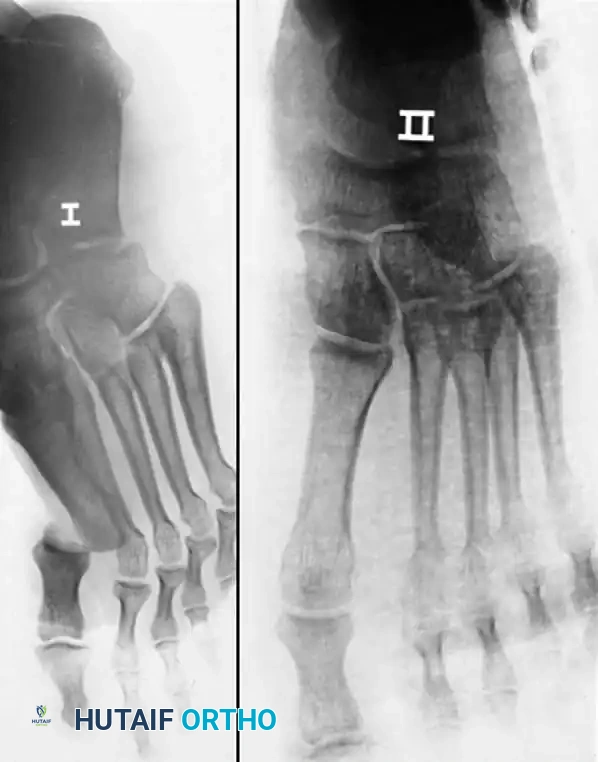

Considerations for Lesser Toes

Historically, interphalangeal joint dislocations of the lesser toes have been highly amenable to closed reduction, followed by buddy taping to the adjacent toe for 3 weeks. However, literature by Brunet and Tubin highlights that a significant subset of these injuries may be more complex. In their series, nearly all dislocated lesser toe IP joints required open reduction due to plantar plate incarceration.

Furthermore, approximately 30% of dislocated lesser toe metatarsophalangeal joints required open reduction. While successfully reduced lesser toe IP joints were virtually asymptomatic at long-term follow-up, residual subluxations or dislocations at the MTP joints remained persistently painful.

For recurrent or highly unstable proximal interphalangeal (PIP) joint dislocations of the lesser toes, resection arthroplasty of the head and neck of the proximal phalanx may be required.

Fig. 86-51 Recurrent dislocation of proximal interphalangeal joint of right fourth toe was treated successfully by resection of head and neck of proximal phalanx and immobilization for 3 weeks.